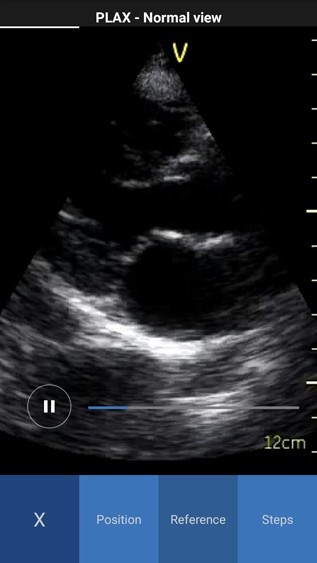

- Reference - Provides access to multiple ultrasound image examples for normal view and a few common pathologies for the current scan plane. You can access all available reference images swiping left or right.

NOTE: By default the reference image tab is activated when you press the info icon for the first time. The white color in the image header represents an example of a normal image, while red color represents an example of a pathology image.

Reference Image Normal